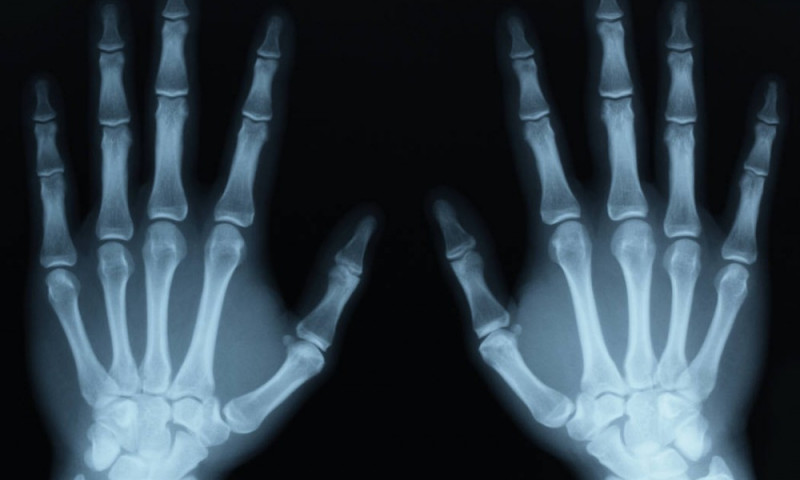

तत्कालिन चर्चित खोज मानिएको एक्सरेको बारेमा रोन्तजेनले विभिन्न प्रस्तुति र प्रकाशन गरेपनि यसको पहिलो मेडिकल प्रयोग भने उनले आफ्नै श्रीमति एन्नाको हातको एक्सरे गरेर गरेका थिए । शुरुमा यसको प्रतिअसर थाहा नभएकाले मानिसहरुले फोटोग्राफी सरह एक्सरेको प्रयोग गरे । झण्डैै १ दशक सम्म मानिसहरुले पैसा तिरेर सौखका लागि एक्सरे गर्ने गरे तर जब विस्तारै यसको असरहरु देखिन थाल्यो तब यसको जथाभावी प्रयोग बन्द भयो । एक्सरेको असर–प्रतिअसरमा साधारण असर देखि शरीरका विभिन्न भागका क्यान्सरसम्म रहेका छन । गर्भवती अवस्था र बच्चामा एक्सरेको प्रयोग संवेदनशिल मानिन्छ, तसर्थ गर्भवति अवस्थामा यसको प्रयोग सकेसम्म न्युन रुपमा गर्नुपर्छ ।

- साधारण रेडियोग्रफीः छाती (Chest), हातखुट्टा (Extremities), कुम (Shoulder), नितम्ब (Hip), मेरुदण्ड (Vertebral column), घाटी (Neck), टाउको (Skull), पिनास (Sinus) आदी